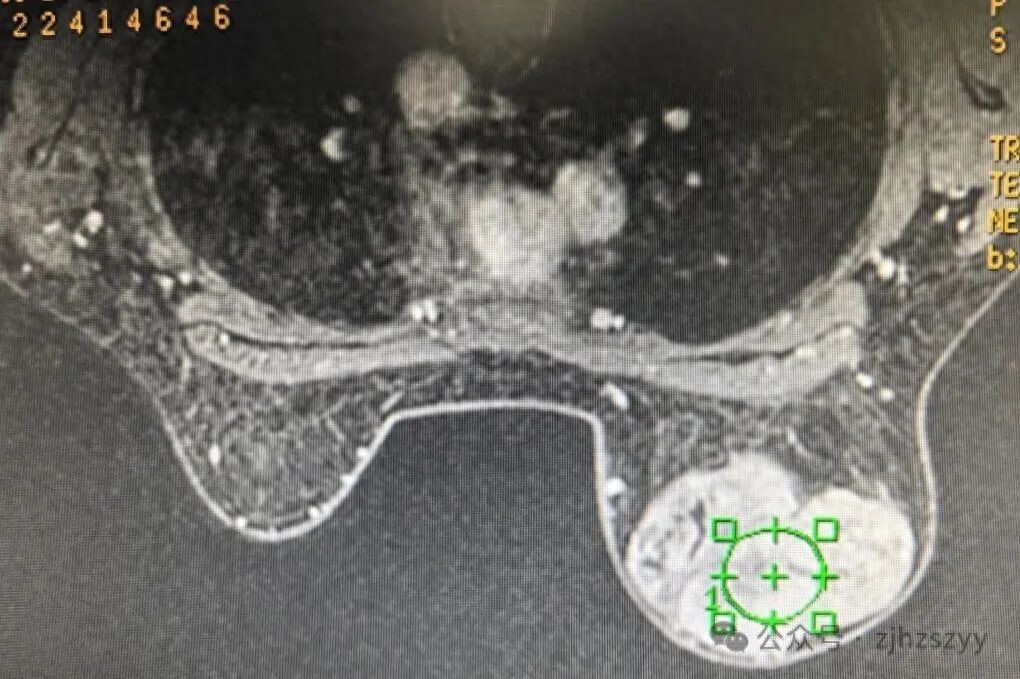

「就是自己摸到的,一開始沒在意,後來慢慢變大了……」入院後檢查發現,小劉的右乳腫塊已達10cm×12cm,幾乎佔據整個乳房,外觀上右乳已明顯大於左側。醫生結合檢查情況,建議她儘快手術切除並進行病理檢查。

葉狀腫瘤是一種生長較快的乳腺腫瘤,因其在顯微鏡下呈現如樹葉脈絡般的分葉狀結構而得名。